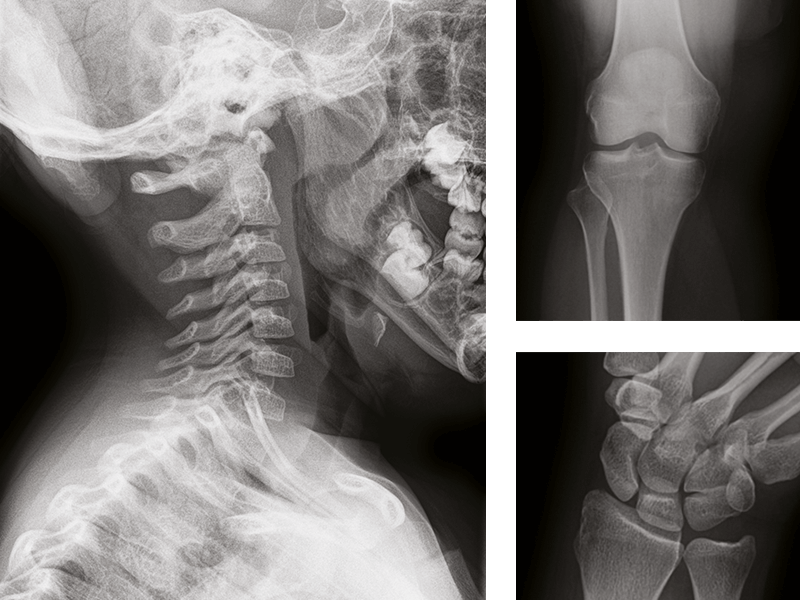

Clear bone and soft tissue presentation across different anatomies and views.

Consistent brightness and contrast

Helix delivers consistent brightness and contrast across variations in dose exposure with Smart Windowing and enhanced Contrast Restoration